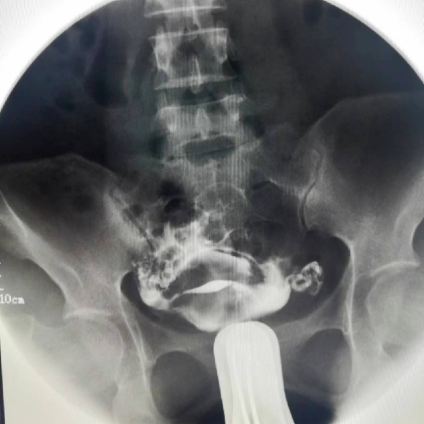

子宮輸卵管造影

實時觀察,有助確定病變類型及位置,檢查損傷小,刺激性小,能顯示子宮變異、子宮輸卵管通暢情況,并對疏通輸卵管有一定的治療作用。